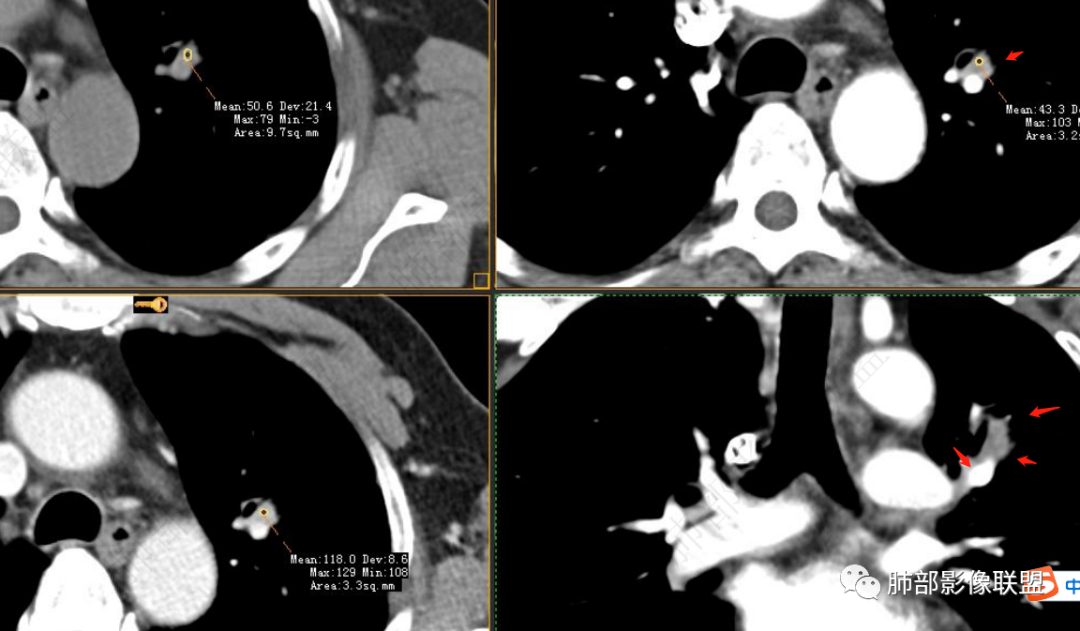

实性部分强化明显,边缘平直

软组织+重建;病灶实性部分不是类圆形,密度相对均匀柔和。

肺门区病灶与支气管关系不密切,强化显著、磨玻璃晕等等容易想到的是肺腺癌。而不首先考虑与支气管密切相关恶性肿瘤,如鳞癌、类癌、粘液表皮样癌等等。